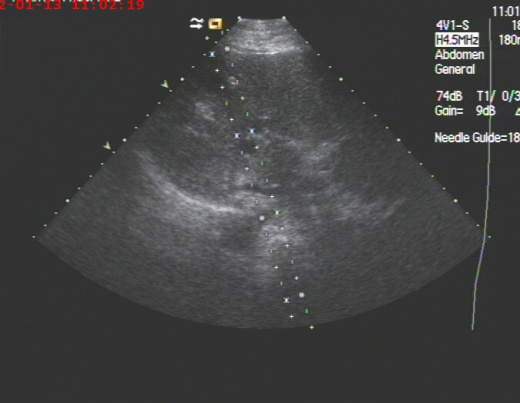

我科开展肝脓肿、胆囊脓肿合并肝脓肿穿刺抽吸及置管术几年来,已治愈多例因高龄无法手术者,或术前减压治疗,后期再进一步手术者,经超声引导下囊肿治疗术已广泛应用于临床,因其具有不用开刀、局部麻醉、安全、痛苦小、疗效好、并发症少等特点,已成为各种囊肿治疗的首选。

通常小囊肿可以观察,但囊肿较大,超过5 cm 且有不适时,则需考虑治疗。目前介入治疗是最为有效的治疗手段,我们在彩超的引导下,进行穿刺,可以有效避开血管,选择最佳路径,经过反复注射无水酒精再抽出就能达到治愈的目的。该项技术对于全身各部位囊肿,尤其卵巢巧克力囊肿效果也非常好。

囊肿穿刺治疗术价格相对便宜,复杂囊肿2-4次可治愈,属于微创介入手术,术后仅有一针眼、创伤小,可以缓解病人痛苦、减轻经济负担,且不影响正常生活,易于患者接受。还可以对宫外孕未破裂前局部注药治疗,免去开刀痛苦。